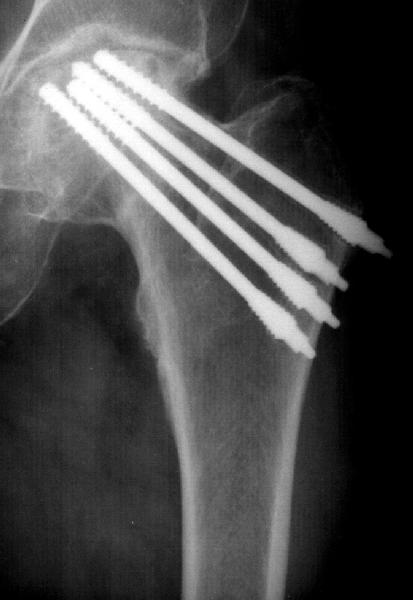

Colleagues from another unit plan to remove the screws and perform THR, so they request advice whether any special instrumentation is needed for the implants removal.

I'm not sure what the implants are, but I bet they could be removed with the instruments in the Synthes broken screw removal set, which include reverse threaded extraction tools of a diameter large enough to engage those screws.